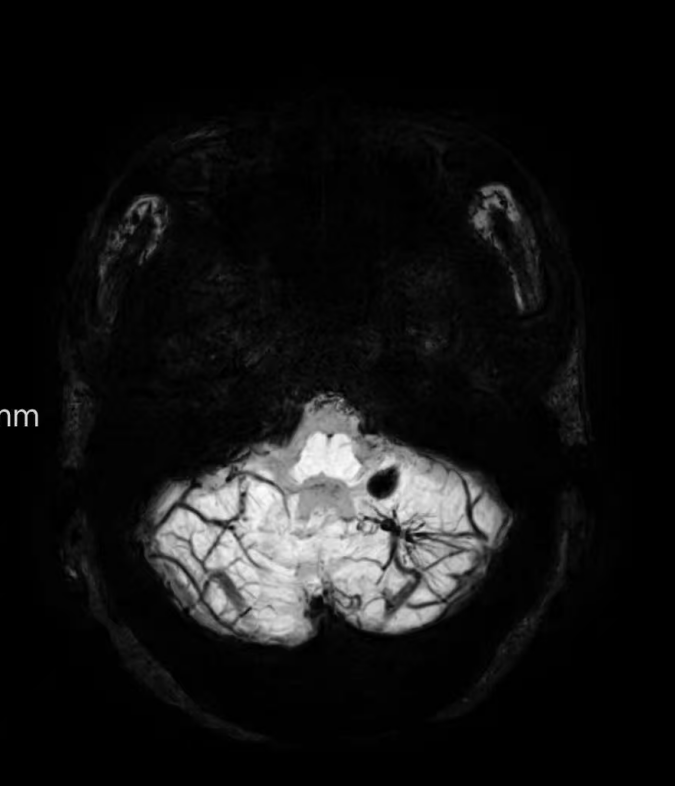

臨床中遇到一位患者,中年女性,反復(fù)出現(xiàn)頭痛,時(shí)輕時(shí)重,常規(guī)CT及磁共振檢查無明顯異常發(fā)現(xiàn),最后建議加做一個(gè)磁共振磁敏感加權(quán)成像(SWI),結(jié)果發(fā)現(xiàn)是左側(cè)小腦發(fā)育性靜脈畸形(DVA),SWI清晰顯示畸形的靜脈及周圍含鐵血黃素沉積;如下圖。這正是她頭痛的原因。

①診斷靜脈畸形:SWI能高精度地顯示發(fā)育性靜脈畸形——一種常見的腦血管畸形。在SWI上,發(fā)育性靜脈畸形會(huì)呈現(xiàn)典型的“海蛇頭”或“水母頭”征,即一堆細(xì)小的髓靜脈匯入一支粗大的引流靜脈。